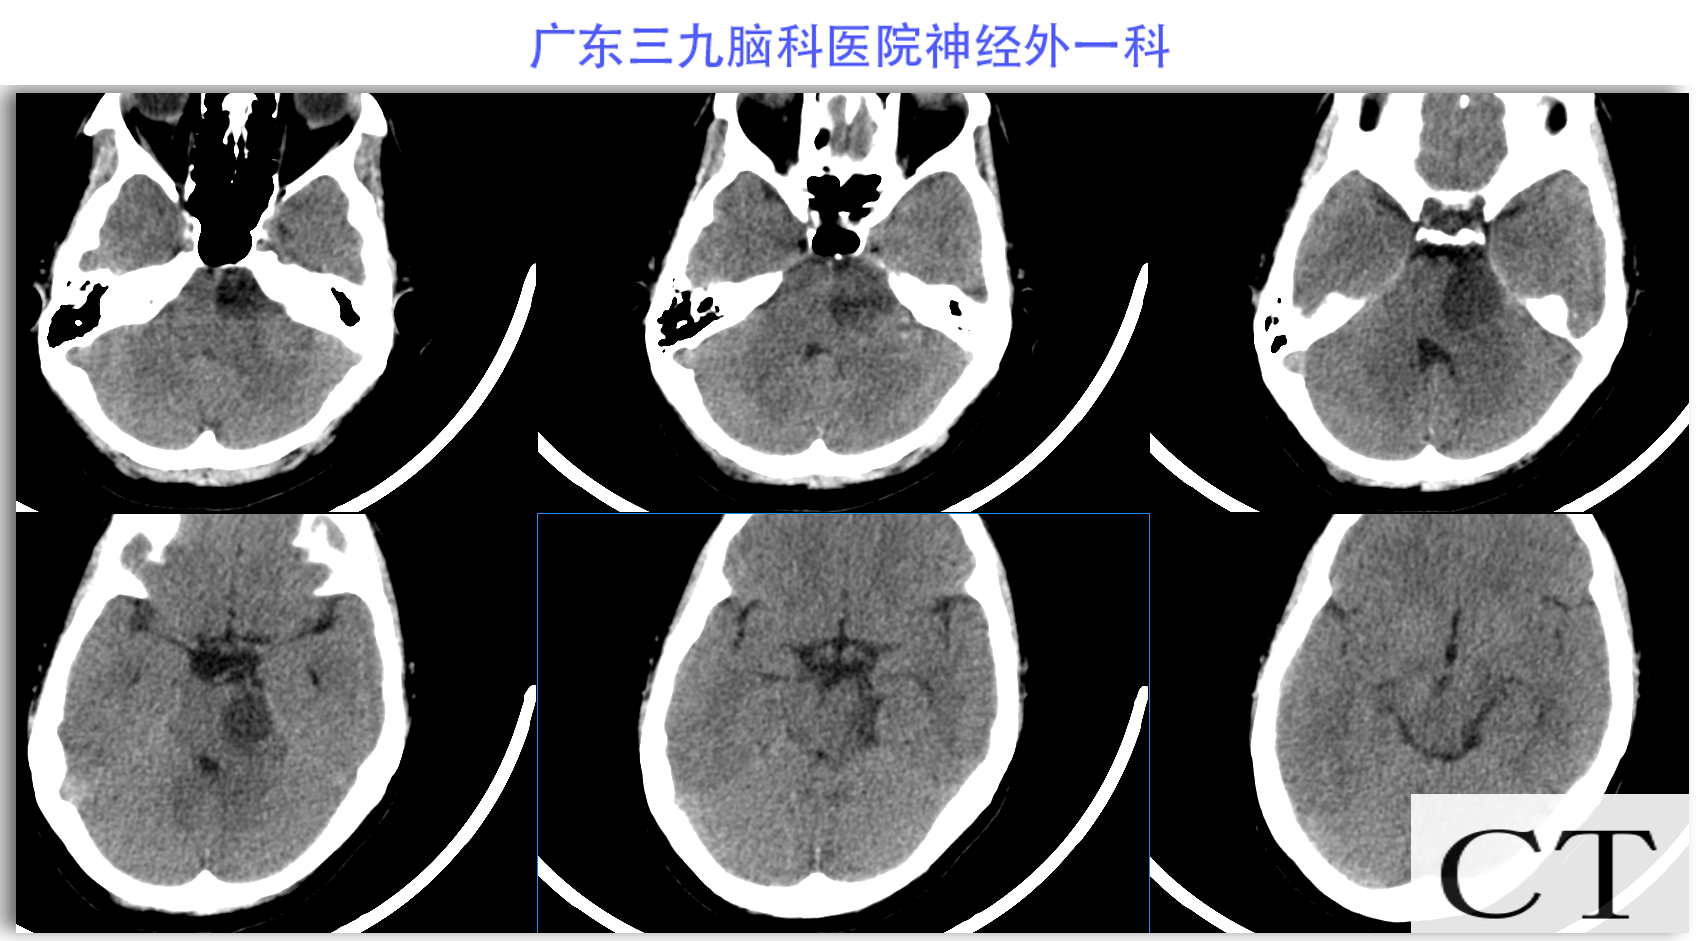

陈某某,女,41岁,因“左侧面部麻木3月余,吞咽困难半月余”于2024-02-17入院。患者3个月前出现左侧面部麻木,偶尔伴有头晕和左侧流泪,但没有听力下降或耳鸣。同时,患者也出现肢体乏力和行走不稳,但未接受任何治疗。半个月前,患者发现吞咽硬质食物稍有困难,同时左侧面部麻木加重。因此,前往当地医院就诊,并进行头颅MR检查,结果显示左侧CPA区存在占位性病变。为了进一步治疗,患者转诊至我院就医。术前检查显示:左侧角膜反射减弱,左侧鼻唇沟略微变浅,伸舌稍微右偏,咽反射迟钝。门诊诊断为“左侧巨大听神经瘤”,收治至我科进行住院治疗。手术过程顺利,术后患者恢复良好,面部轻度瘫痪与术前相同。术后病理检查结果确认为听神经瘤。